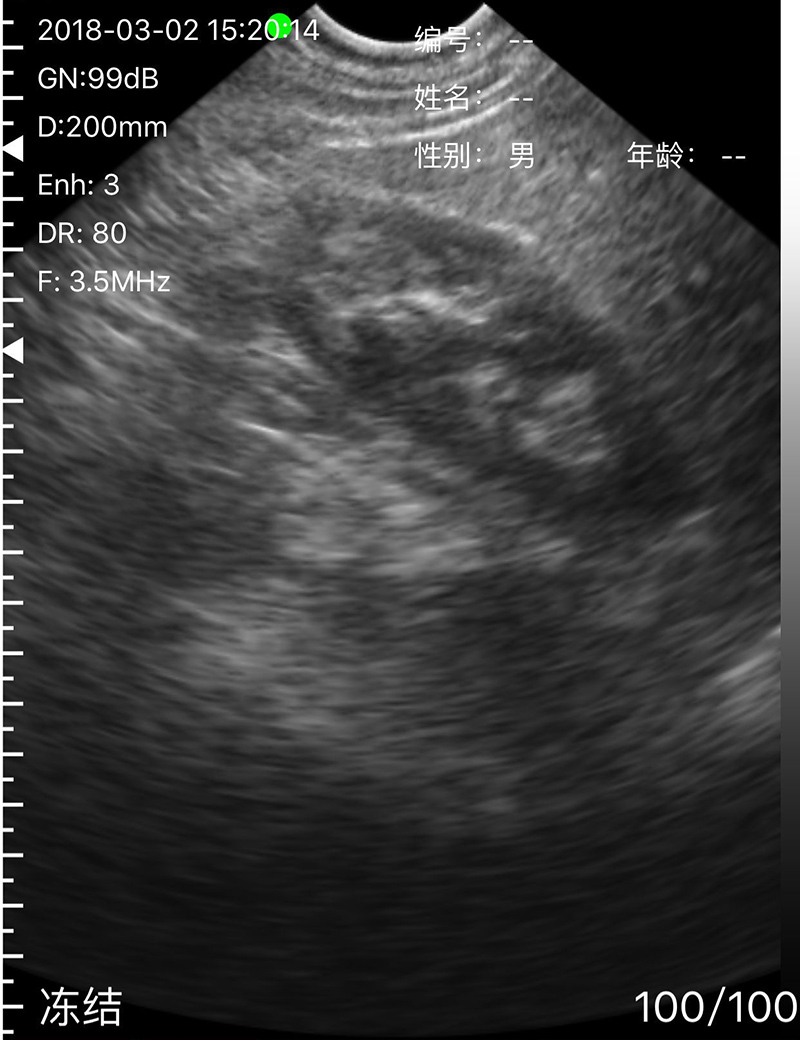

• Scan mode: Electronic Array, convex with cardiac namely phased array or linear array scanning;

• Frequency: Micro-Convex probe 5.0/7.0MHz, Linear probe 10/12MHz

• Scanning Depth: Micro-Convex 60-160mm, Linear 20-80mm, adjustable